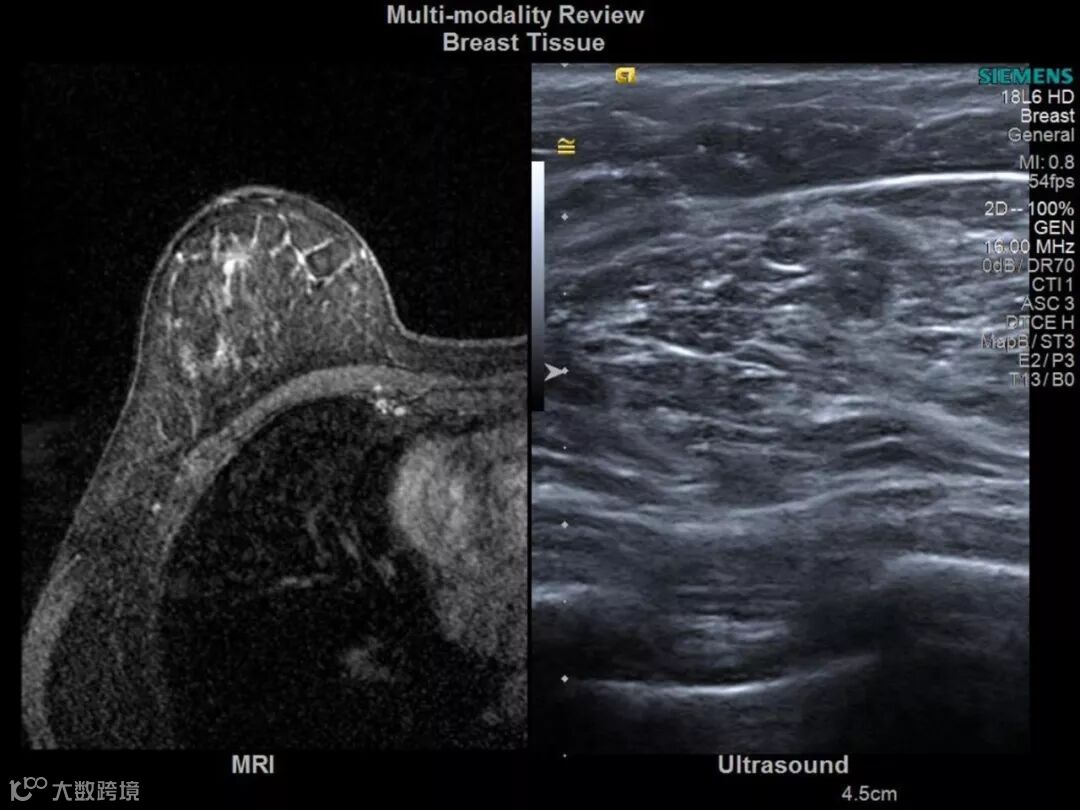

2001年,西门子收购美国超声巨头ACUSON公司,建立全新的ACUSON超声产品线,原有SONOLINE系列超声逐步退出市场,西门子通过美中互利和蓝韵布局中国市场,美中互利为其国内中高端彩超代理,蓝韵代理西门子的X150(2007年)低端彩超。

015年西门子宣布将西门子医疗部门独立,并且随后更名为Siemens Healthineers,2017年Siemens Healthineers于德国法兰克福证券交易所挂牌上市交易。近年来,公司不断加大研发力量的投入,相继为中国及全球医疗用户研发并推出了双排、6排、16排到最新的64排(128层)螺旋CT,以及数字X射线成像系统、数字胃肠机、骨科C臂等多种X光影像设备。以CT产品为例,全球销售的每两台西门子CT中,就有一台来自于上海西门子医疗器械有限公司。我们的CT约70% 出口到包括欧盟、美国、日本、韩国等全球150多个国家和地区。同时公司也是西门子医疗全球X光基础医疗产品的研发中心。